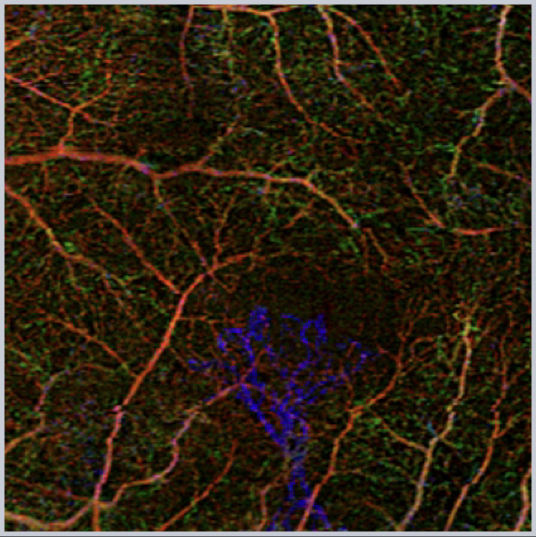

OCT-Angiography is a transformative technology that allows us to look at the chorioretinal vasculature in new ways. By using motion contrast and analyzing patterns of flow we can obtain a non-invasive image of the eye.